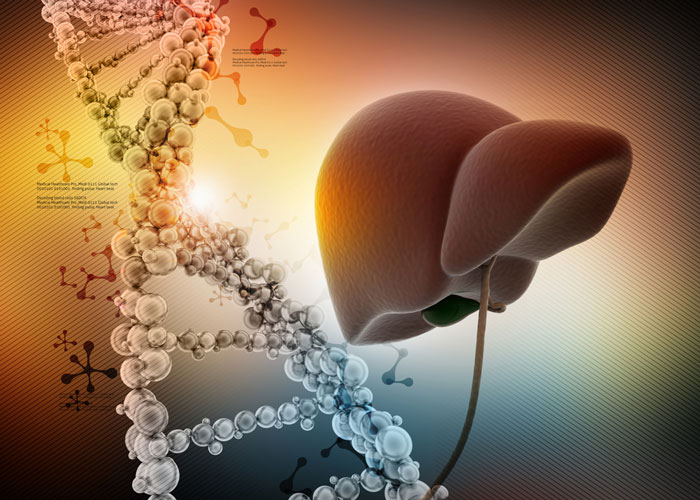

Scientists create advanced 3D liver model mimicking real tissue

Scientists have developed a 3D liver model, known as the periportal assembloid. This model replicates the liver’s complex structure and bile transport system, enabling more precise study of disease progression.